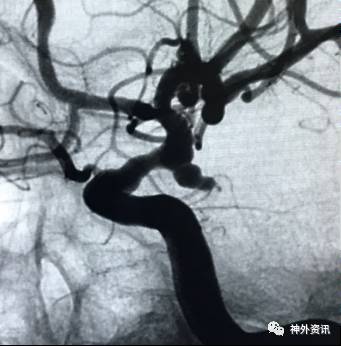

病例一

病例二

病例三

病例四